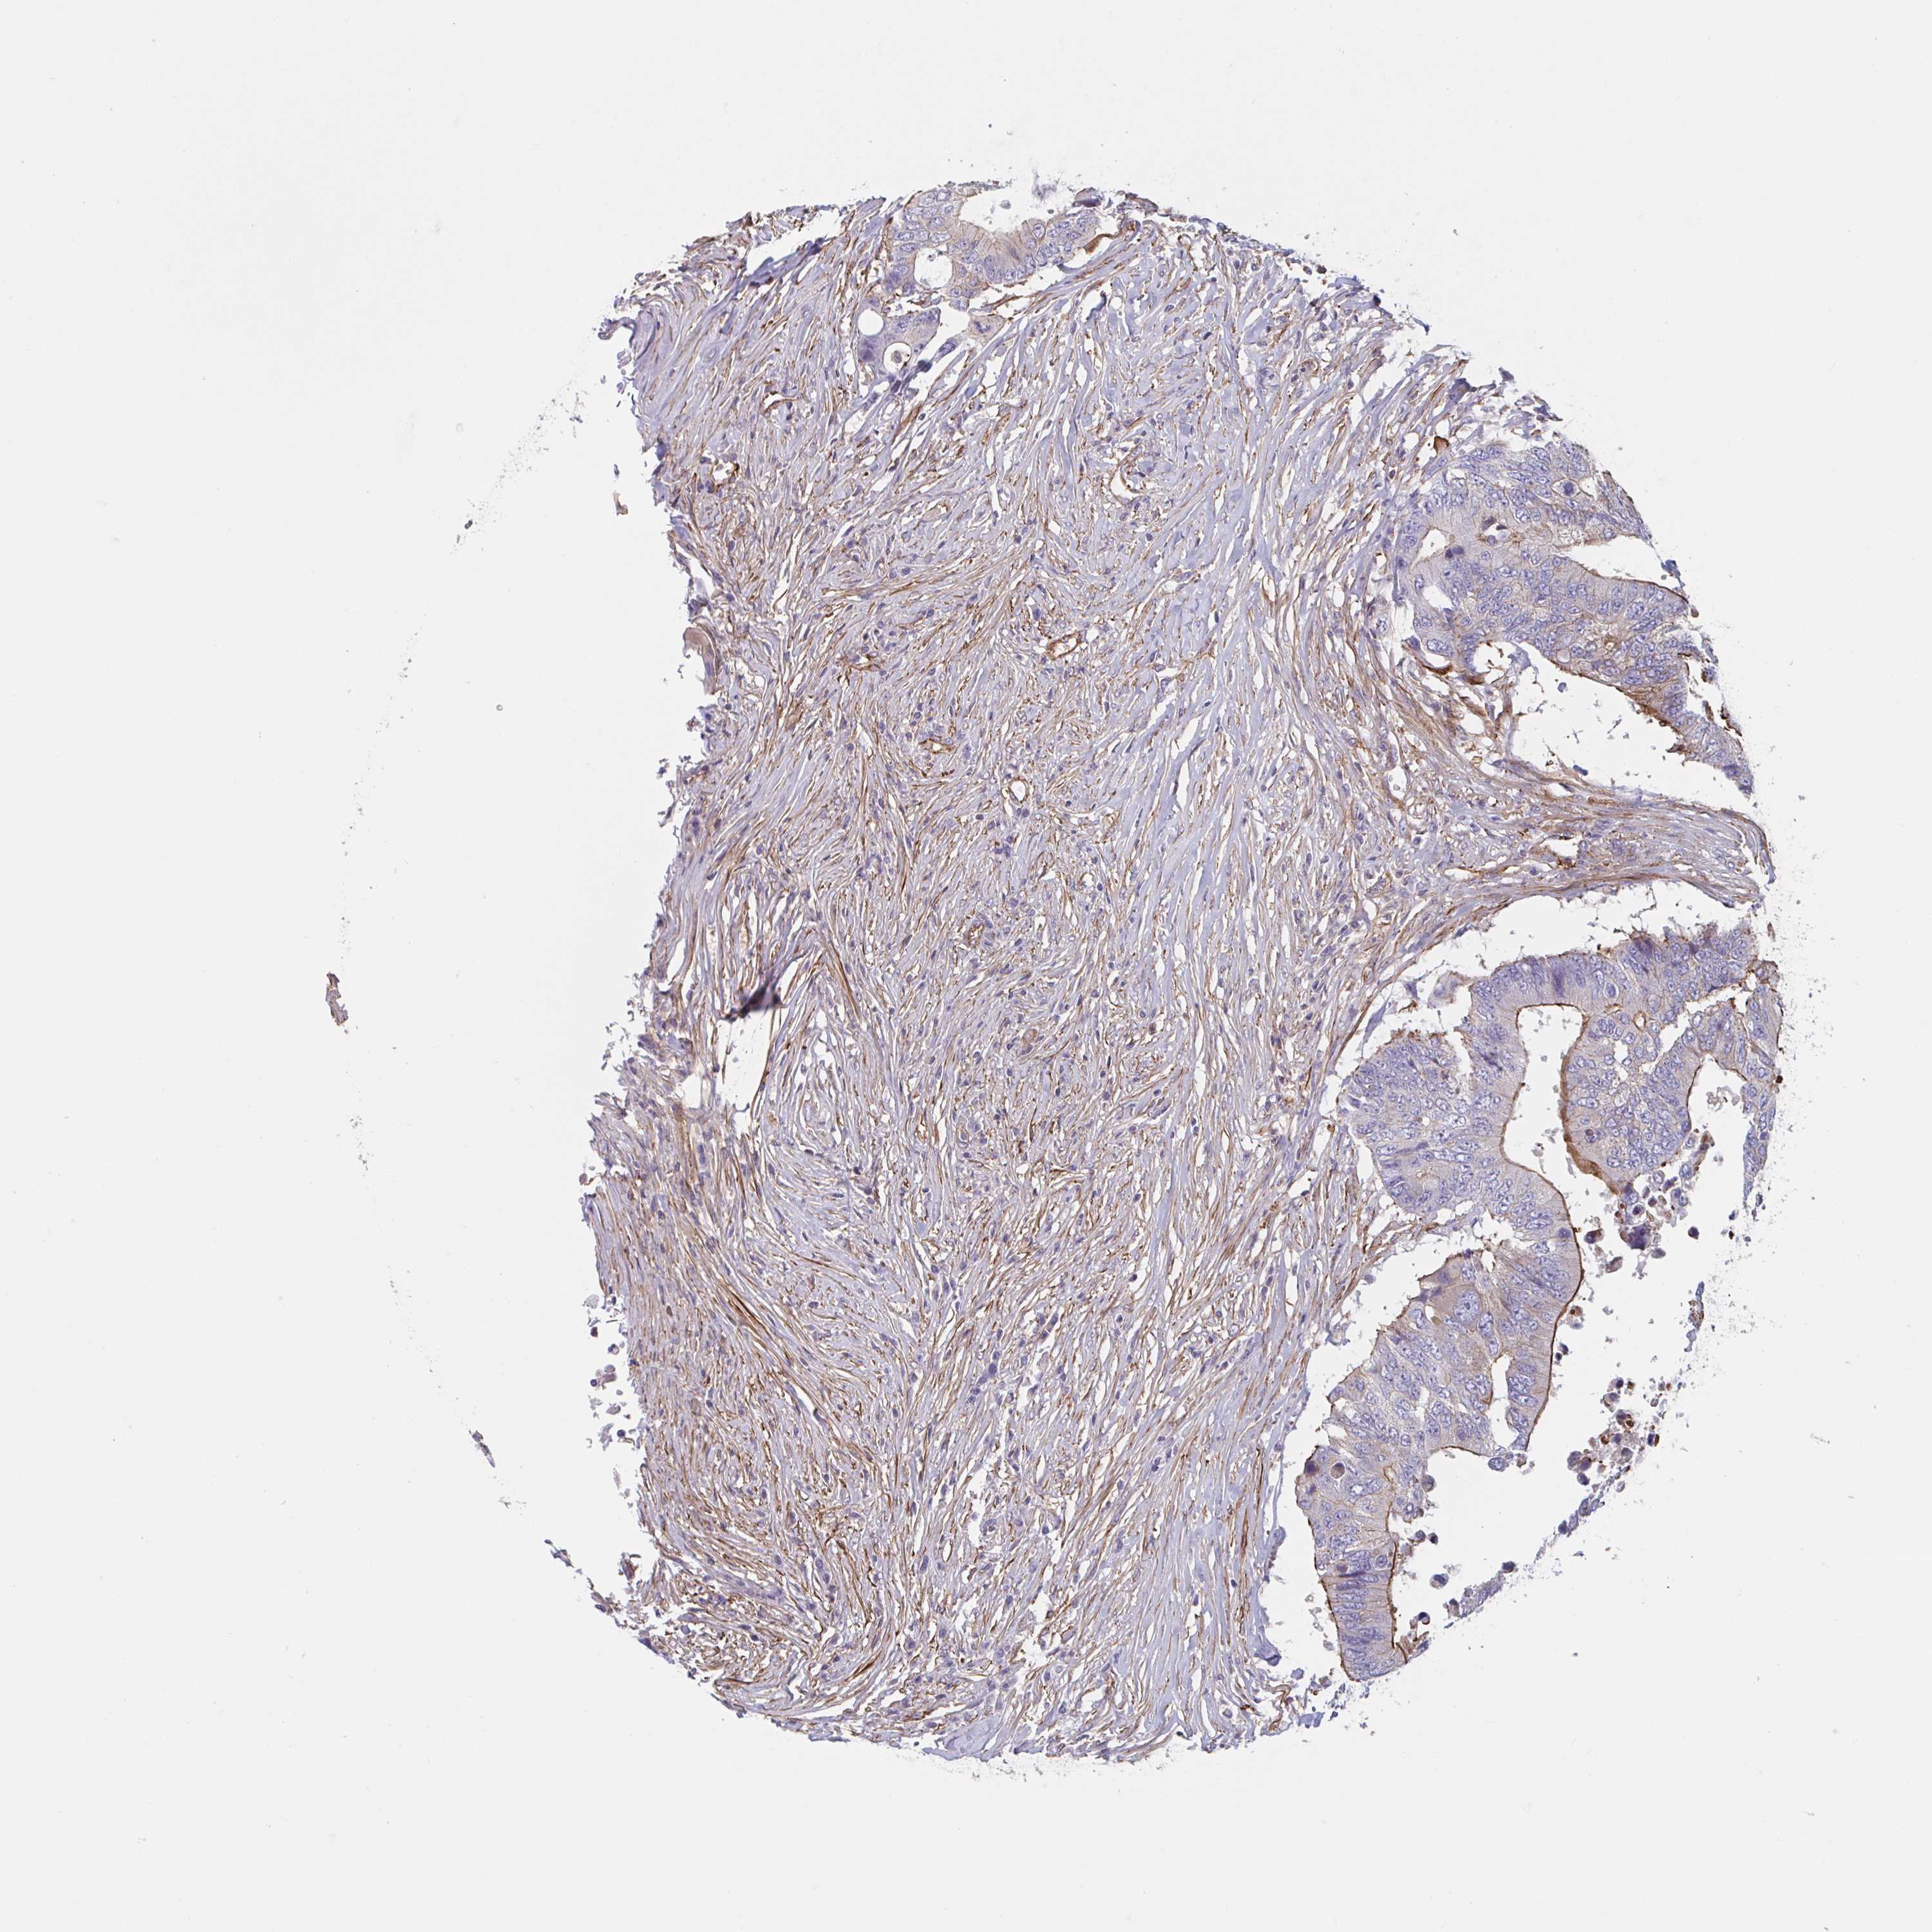

CANCER COLORECTAL CANCER Show tissue menu

Colorectal cancer

Human cancer

Colon adenocarcinoma